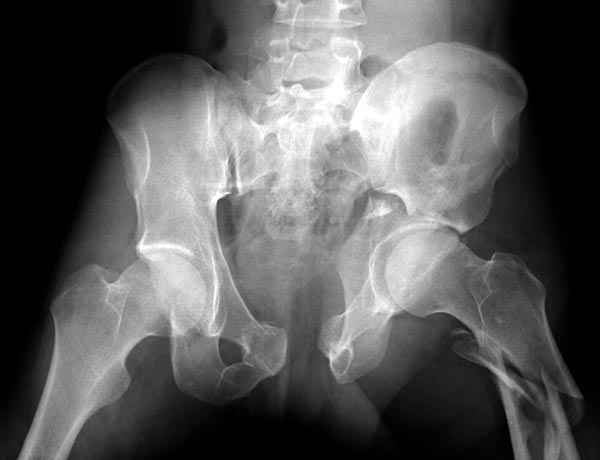

Интересно было бы посмотреть рентгенограммы до операции. У меня впечатление, что я не все вижу, что тут есть... Уважаемые Господа "тазисты" и "тазологи", к какому типу переломов вертлужной впадины по Летурнелю вы бы отнесли это случай?

Судя по представленным реконструкциям (не очень хорошего качества - много наводок)

мы имеем дело с полупоперечным переломом у которого отломался задний край или его отломали, превратив перелом в полный двухколонный.

Поэтому хотелось бы дообследовать больного (разумеется включив стандартные проеции judet,и срезы показывающие сращение)

И наконец главное- какие жалобы у пациента, он нагружает ногу или нет, какая клиника, что-то все рентгенограмму бросились лечить?

Пациент передвигается с помощью костылей с дозированной нагрузкой на правую ногу. При движении правой нижней конечностью ощущает щелчки. Болей в правом тазобедренном суставе в настоящее время нет. Вся правая нижняя конечность умеренно ротирована наружу.

Хорошо бы на рентгенограммы взглянуть и побольше срезов по своду. С каким отломком головка контактирует и как ее состояние.